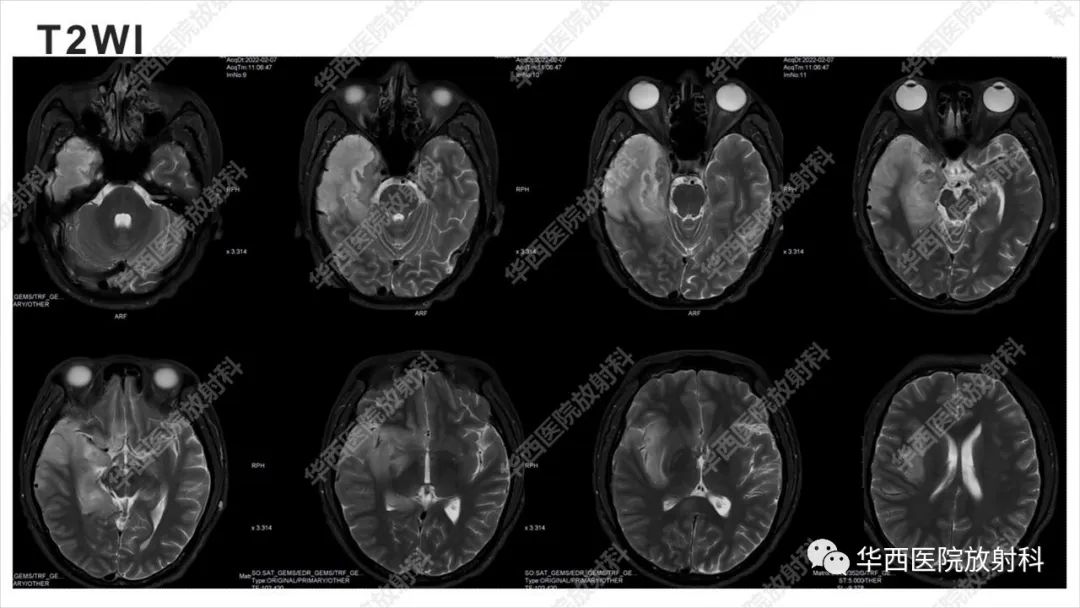

【病例】出血坏死性病毒脑膜脑炎1例CT及MR影像学表现和鉴别诊断-3